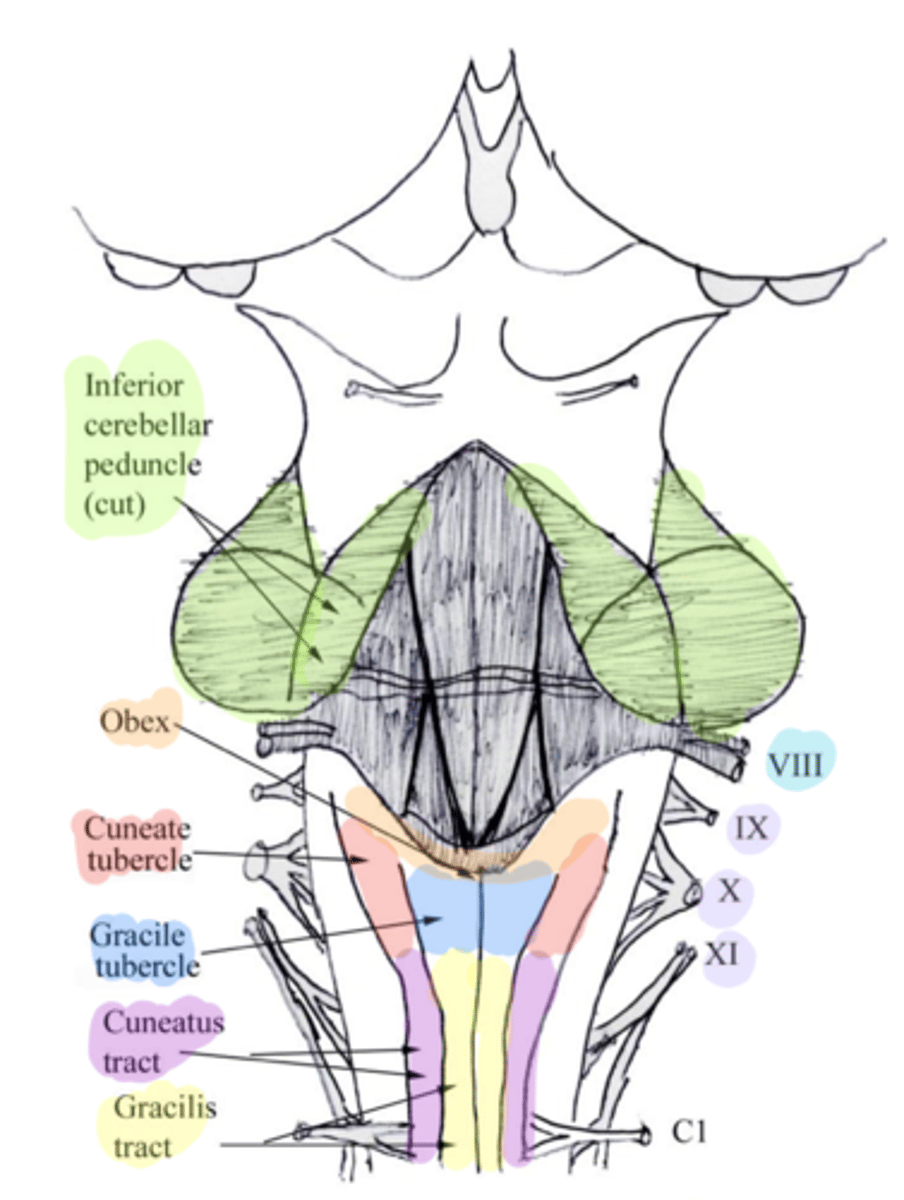

white matter stalks that connect the medulla to the cerebellum

**these help to form the lateral walls of the caudal portion of the 4th ventricle

inferior cerebellar peduncles

medial paired ridges of tissue on the dorsal aspect of the closed portion of the medulla

tractus gracilis

lateral paired ridges of tissue on the dorsal aspect of the closed portion of the medulla

tractus cuneatus

superior ends of the medial paired ridges of tissue on the dorsal aspect of the closed portion of the medulla, formed by namesake nuclei

gracilis tubercles

superior ends of the lateral paired ridges of tissue on the dorsal aspect of the closed portion of the medulla, formed by namesake nuclei

cuneatus tubercles

V-shaped boundary of the caudal aspect of the 4th ventricle that marks the boundary between the open and closed portions of the medulla

obex

inferior cerebellar peduncles

cuneate tubercle

gracilis tubercle

cuneatus tract

gracilis tract

obex

What anatomical aspect of the 4th ventricle is considered its floor?

ventral

refers to the floor of the 4th ventricle

rhomboid fossa

What forms the floor (rhomboid fossa) of the 4th ventricle?

dorsal surfaces of pons tegmentum and open medulla

inferior angle of the floor of the 4th ventricle

obex

vertical groove running in the floor of the 4th ventricle that separates it into right and left halves

dorsal median sulcus

vertical groove lateral to the dorsal median sulcus of the 4th ventricle

**same one that separated the alar and dorsal plates in the neural tube during development

sulcus limitans

refers to most of the floor of the 4th ventricle lateral to the sulcus limitans

**namesake nuclei are here

vestibular area

triangular region located in the caudal portion of the rhomboid fossa of the 4th ventricle, where the dorsal motor nucleus of CN X is

vagal trigone

Which parasympathetic nucleus is found in the vagal trigone of the 4th ventricle?

dorsal motor nucleus of X

triangular region located most medially in the caudal portion of the rhomboid fossa of the 4th ventricle, where the CN XII nucleus is

hypoglossal trigone

part of the 4th ventricle superior to the vagal and hypoglossal trigones (still medial to the sulcus limitans)

medial eminence

small bump located in the caudal portion of the medial eminence which forms from the motor fibers of CN VII as they wind around the underlying CN VI nucleus

facial colliculus

pigmented area that looks blue near the superior aspect of the sulcus limitans; cluster of noradrenergic cells

locus ceruleus

fibers that run horizontally in the central region of the rhomboid fossa of the 4th ventricle

stria medullares

area that helps to make the walls of the obex and is thought to be the "vomit trigger"

area postrema